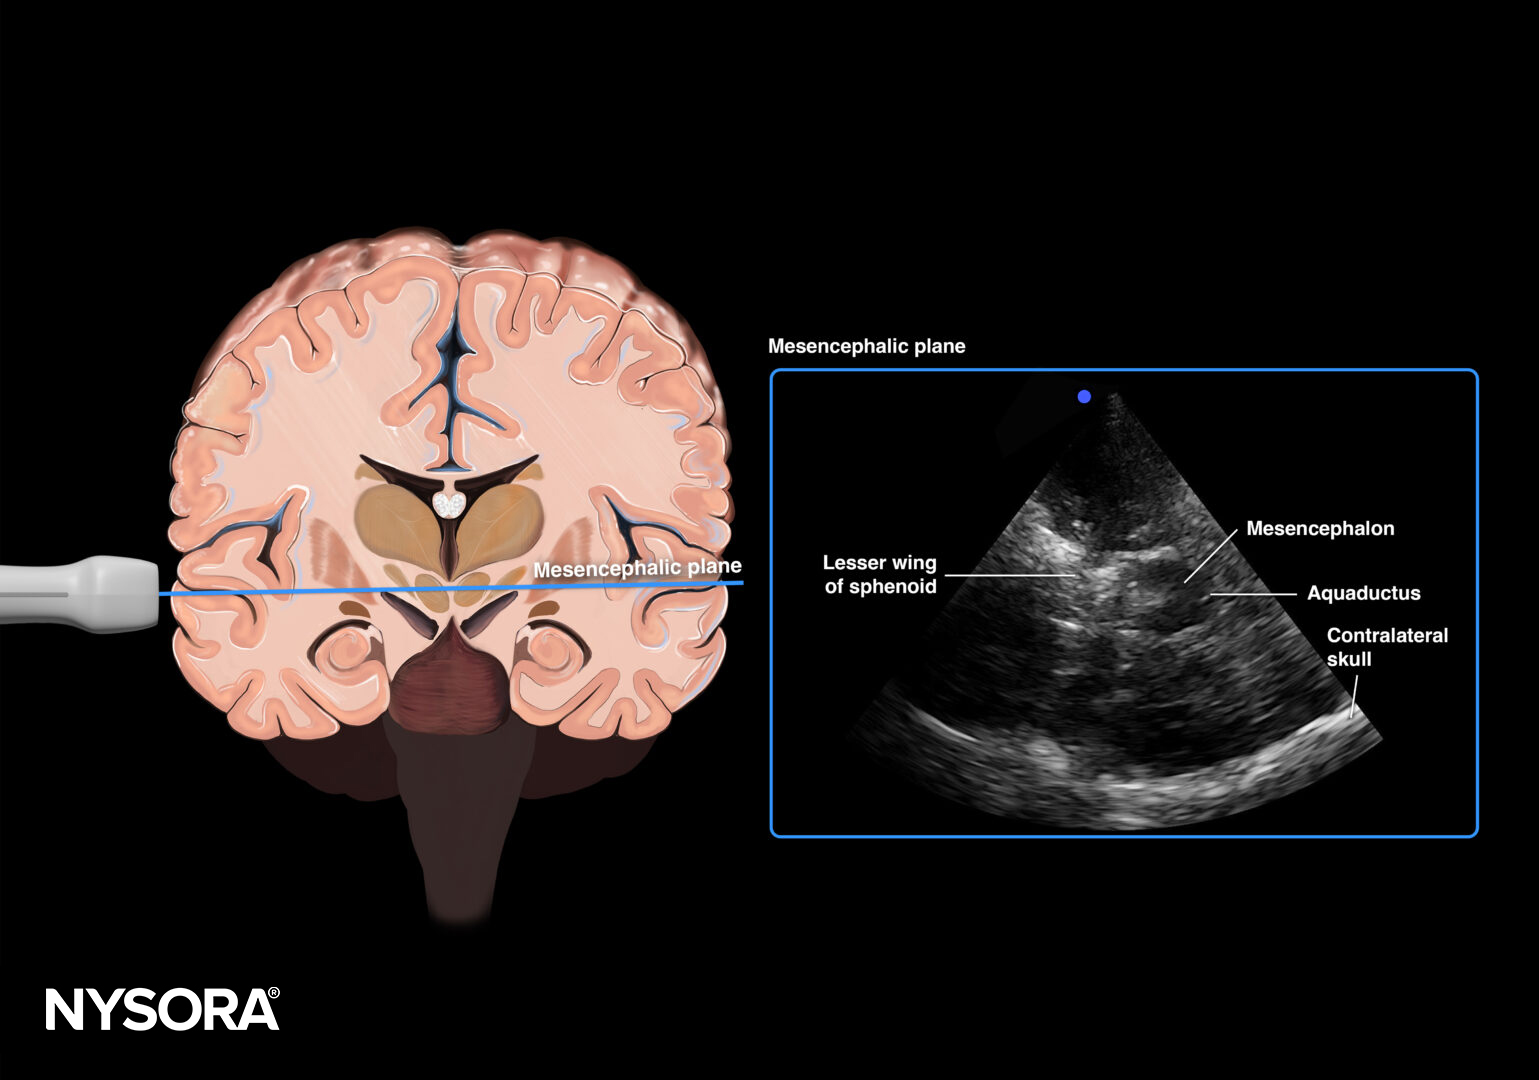

Transducer position for transcranial Doppler examination of intracranial hypertension.

Mesencephalic plane.